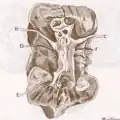

Opuscula, 1695

Opuscula, 1695 Drawing of kidney ducts by Lorenzo Bellini.

Drawing of kidney ducts by Lorenzo Bellini.